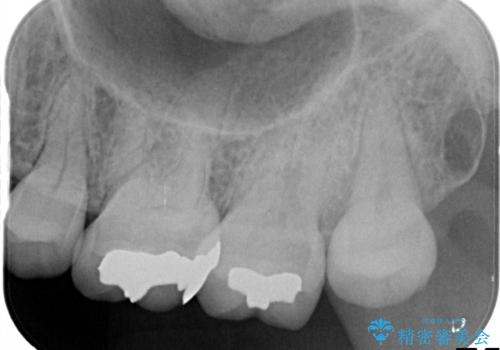

- メタルフリーを主訴に来院されました。

歯牙の破折を防ぐために、セラミッククラウンにて修復しています。